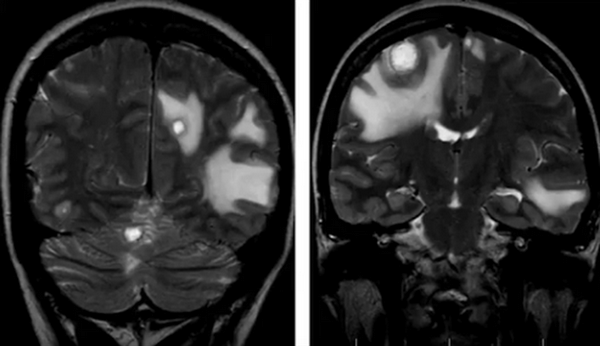

- астроцитомы — происходят из глиальной ткани, чаще выявляются в лобных и височных долях. Выглядят как зоны гипоинтенсивного МР-сигнала без четких контуров, плохо или почти не накапливают контраст, нередко содержат в своей структуре обызвествленные зоны и мелкие кисты;

- олигодендроглиомы — плотность снижена неравномерна, контуры относительно четкие, часто сливаются с отеком. Обнаруживаются в лобной или теменной долях.

- эпендимомы — предположительно образуются в эмбриональном периоде. Характеризуются четкими контурами, плотнее, чем здоровые ткани, редко вызывают отек, чаще обнаруживаются в полостях желудочков;

- менингиомы (оболочечные опухоли). На снимках часто дают изоинтенсивный сигнал, отчетливо видны после контрастирования. Имеют четкие контуры, неправильную бугристую форму, обычно нет выраженной зоны перифокального отека;

- метастазы. Выглядят, как множественные образования в тканях головного мозга различных размеров, неправильной формы, с неровными контурами, накапливающие контраст, с различной интенсивностью отека вокруг;

- невриномы — опухоли черепно-мозговых нервов. Чаще исходят из корешка VIII пары, реже V и остальных. На Т2-взвешенном изображении гиперинтенсивны по сравнению с окружающими тканями. Контуры неправильные, четкие, структура гомогенная, дают масс-эффект.